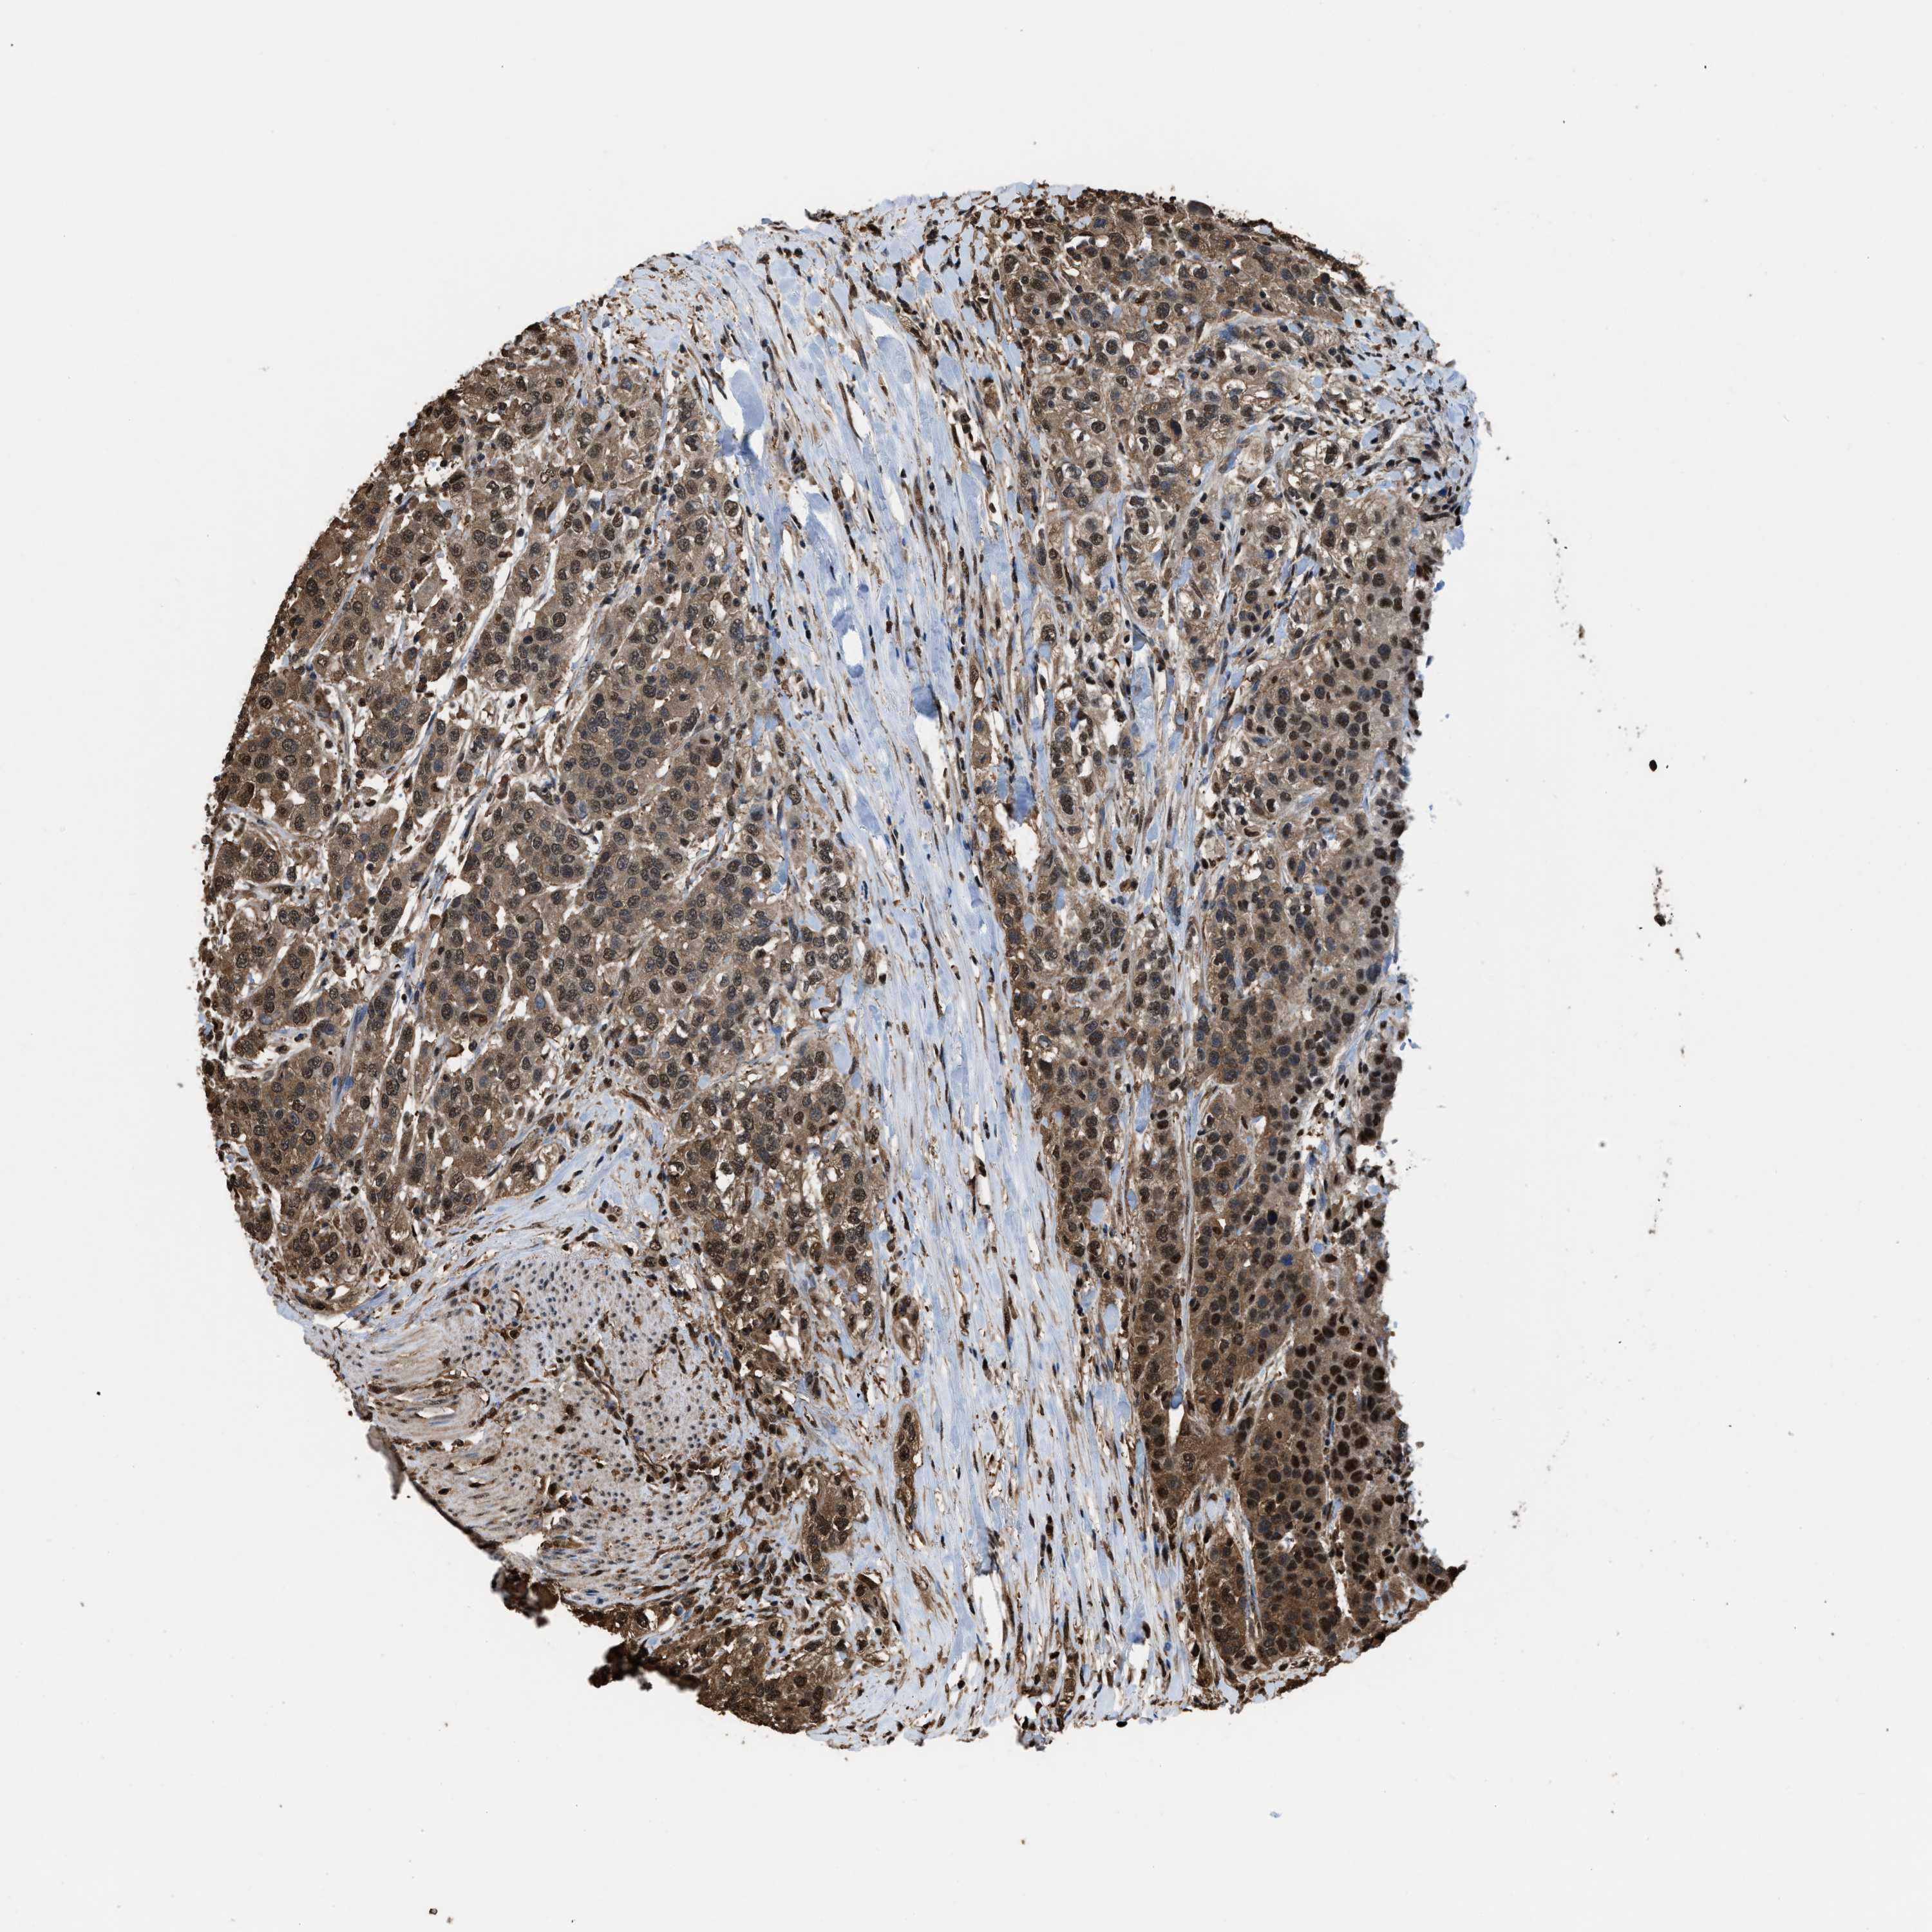

UROTHELIAL CANCER - Protein expressioni

A mouse-over function shows sample information and annotation data. Click on an image to view it in a full screen mode. Samples can be filtered based on level of antibody staining by selecting one or several of the following categories: high, medium, low and not detected. The assay and annotation is described here.

Antibody stainingi

Antibody staining in the annotated cell types in the current human tissue is reported as not detected, low, medium, or high, based on conventional immunohistochemistry profiling in selected tissues. This score is based on the combination of the staining intensity and fraction of stained cells.

Each image is clickable and will lead to virtual microscopy that enables deeper exploration of all samples and also displays staining intensity scores, fraction scores and subcellular localization as well as patient and tissue information for each sample.

Antibody HPA018830

Antibody CAB010149

Staining

High

Medium

Low

Not detected

Intensity

Strong

Moderate

Weak

Negative

Quantity

>75%

75%-25%

<25%

None

Location

Nuclear

Cytoplasmic/membranous

Cytoplasmic/membranous,nuclear

Urothelial carcinoma, Low grade

Urothelial carcinoma, High grade